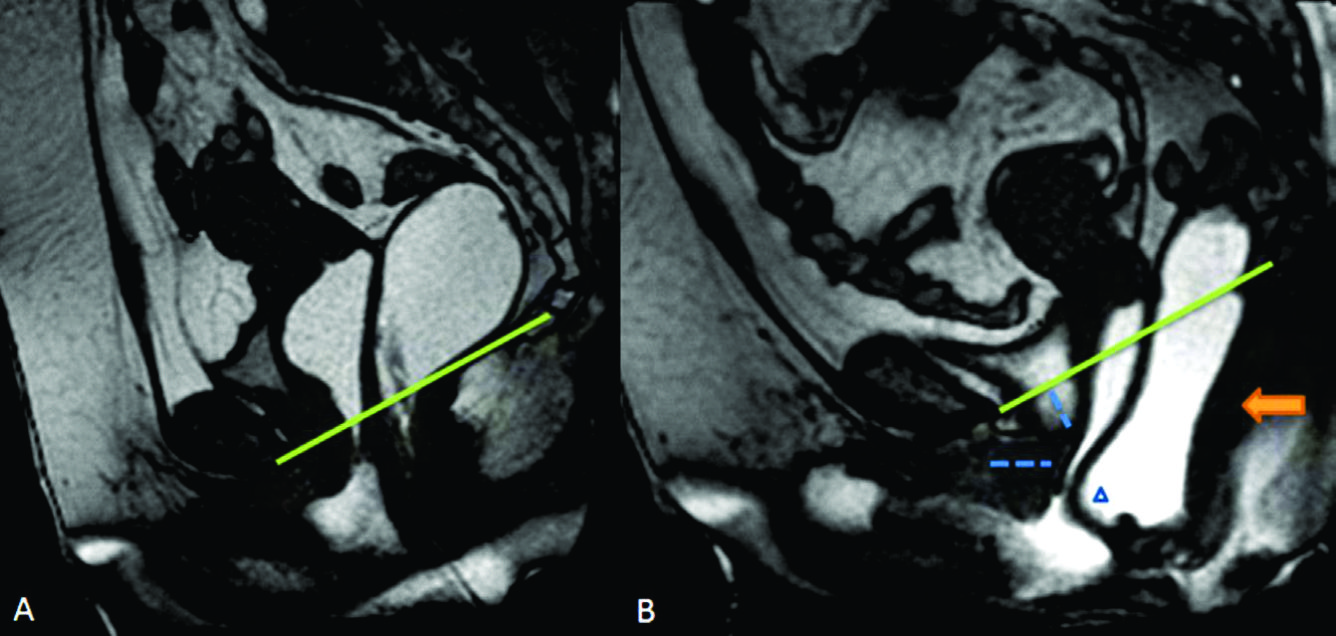

Figura 7

Rectocele anterior y cistocele.

Imágenes TRUE FISP de alta resolución en el plano sagital a nivel de la línea media de una mujer durante A) el reposo y durante B) la defecación. En B se observa angulación caudal del plano del elevador (flecha naranja), rectocele anterior (triangulo) y cistocele con hipermotilidad uretral (punteado azul en B).